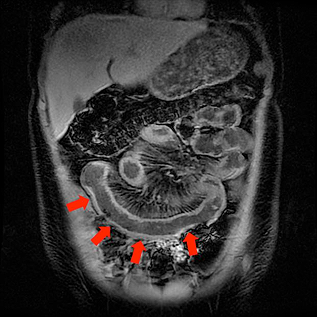

Inflammatory bowel disease (IBD) (including Crohn’s disease and Ulcerative Colitis) affects both adults and pediatric patients with an estimated 10,000-47,000 new cases diagnosed each year. Up to 1/3rd of these cases are in the pediatric population [1,2]. This condition causes inflammation of the small and large bowel, leading to complications such as infection and bowel obstruction. Patients will endure bouts of remission interrupted by acute flares of inflammation. This can lead to multiple visits to the emergency department. More often than not, imaging is also performed during these visits. In a patient with IBD, these patients may undergo multiple imaging examinations over the course of their lifetime. In a pediatric patient with this diagnosis, the number is even greater. It is for this reason that any exposure to ionizing radiation should be minimized and alternative non-radiation methods should be employed whenever possible. MR enterography, a non-radiation method of examining the bowel, has recently emerged as highly effective method of assessing disease in these patients.

MR enterography uses Magnetic Resonance Imaging (MRI) with oral and intravenous contrast to assess the entire abdomen and pelvis including the bowel. This allows the radiologist to see processes both inside and outside the bowel, all without the use of ionizing radiation. At the UCSF Benioff Children’s Hospital, we have optimized our MR enterography examination to evaluate patients across a broad age range. This even includes the addition of flavor additives to our oral contrast to improve taste of the oral contrast!